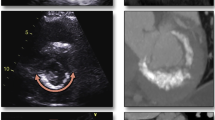

Chest X-ray (Fig. 1) may show a C-, J-, U-, or O-shaped radiopaque image in the mitral annulus, usually with its opening directed to the aortic valve. Because of the left pulmonary veins, sometimes it is better visualized in lateral projections [5].

On M-mode echocardiography, MAC is seen as an echo-dense band near the mitral valve, usually beneath the posterior leaflet, anterior and parallel to the left ventricular free wall. On 2D echocardiogram (Fig. 2), it is seen as an irregular, echo-dense shell-like structure that produces acoustic shadowing [11, 38]. The calcific deposits are most often seen in the posterior part of the annulus, evenly distributed. When it occurs in the anterior region, it tends to be in the medial segment [39].

MAC can be visualized and quantified from a single computed tomography (CT) image acquisition (Fig. 4) without additional contrast agents [41]. Electrocardiogram (ECG)-gated cardiac CT is a useful tool to measure the extent and location of MAC and to plan the surgery when indicated. It can accurately show areas where there is more calcium, where it does not allow suture, and where it is safe to do. It can also predict the need for decalcification and reconstruction of the annulus, providing vital anatomical information reducing periprocedural risk of complications [21, 42]. In patients undergoing transcatheter mitral valve replacement (TMVR), cardiac CT is crucial to evaluate the left ventricle outflow tract (LVOT) to predict obstruction after valve implantation [43•].

MAC can be classified as mild (focal, soft echodensity of the mitral annulus, < 180° of total annular circumference), moderate (more prominent echodensity of the annulus, < 270° of total annular circumference), or severe (marked echodensity involving more than 270° of circumference of the mitral annulus or progressing to LV inflow tract or thickness > 4 mm) [45, 46••].